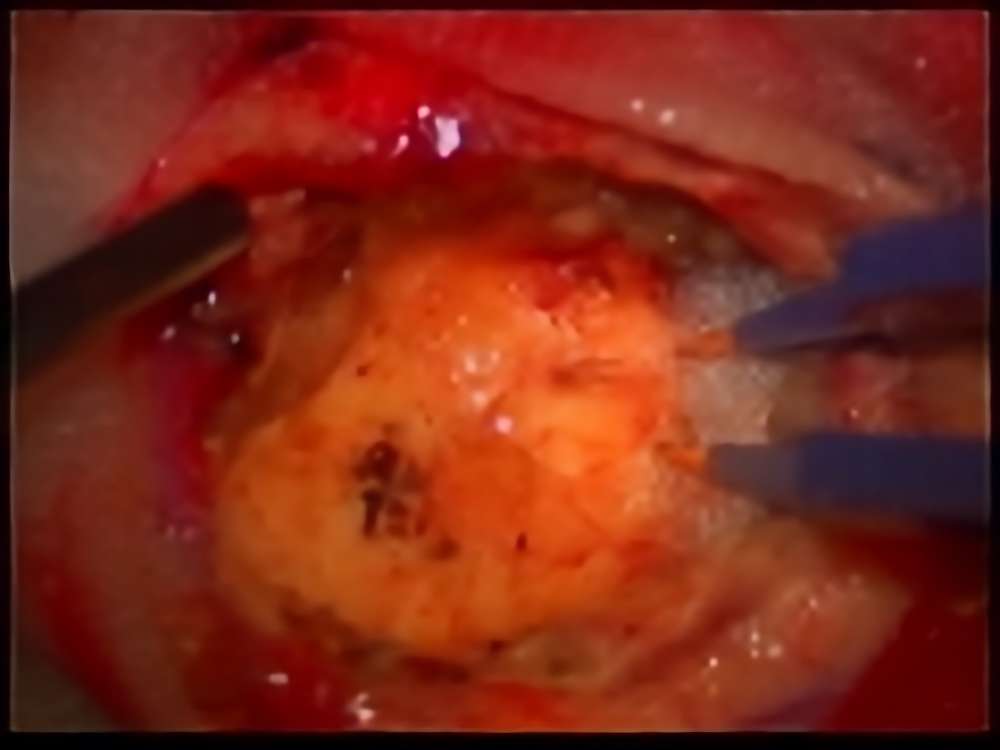

No.’15_13 摘出 前

No.’15_13 摘出 後